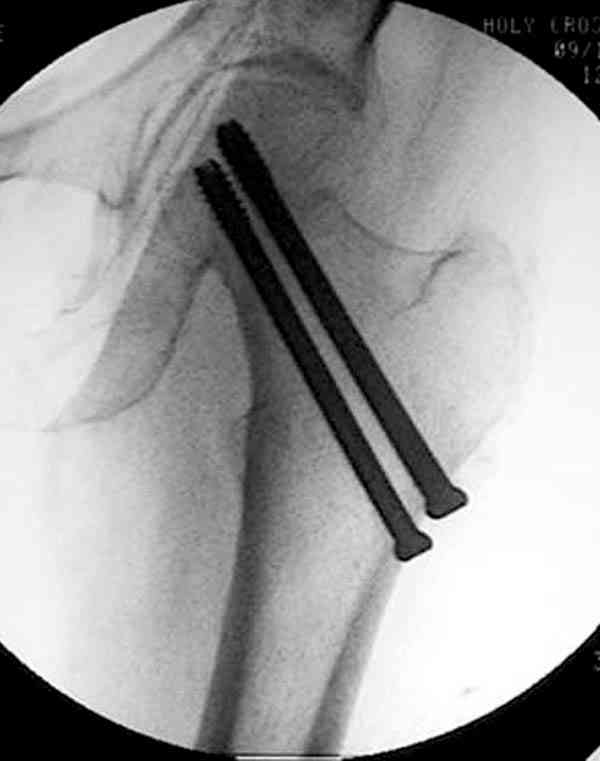

Здесь случай перелома из-за ослабления латерального кортекса через 3 недели после операции на шейке. Шурупы были установлены под большим углом, слабый латеральный кортекс не выдержал нагрузку.